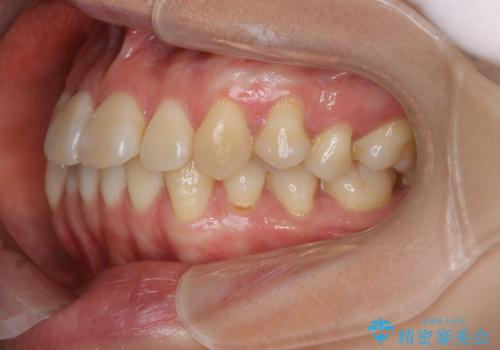

- 前歯のがたつきが気になるとご相談にいらした方です。右側前歯部のクロスバイトの他、左側にもシザーズバイトが認められたため、インビザラインにて治療を行いました。出産直後のため、ご自身の時間がなかなか取れないとの事で、最小限の来院回数で治療を勧められるように計画しました。

患者様ご自身で使用時間をしっかり管理して頂くことを条件に、最低限の来院回数で治療を進めていきました。20時間以上の使用を厳守して頂けたことで、少ない来院回数にて治療を終了することが出来ました。前よりも噛みやすくなったと大変喜んでいただけました。